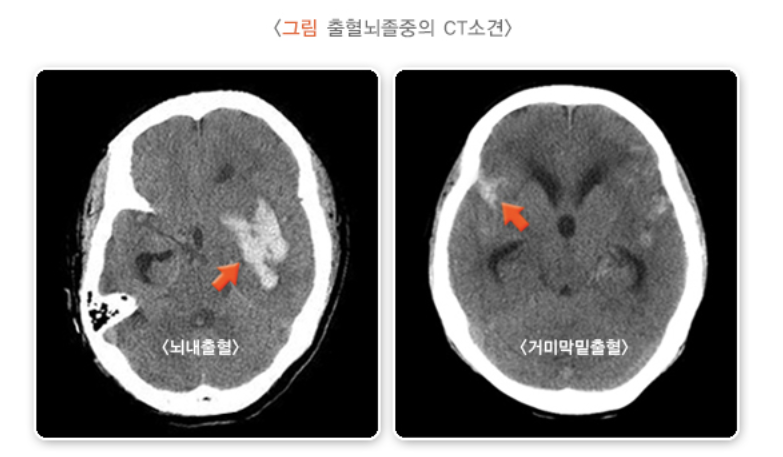

2. 뇌출혈 (출혈 뇌졸중)

- 뇌내출혈 - 갑자기 뇌내 혈관이 터지면서 뇌 안에 피가 고이는 병입니다. 고혈압이 원인입니다. 오래된 고혈압은 뇌내 소혈관을 손상시킬 수 있는데, 손상된 뇌혈관은 스트레스나 압력에 취약해져 잘 터질 수 있습니다.

- 거미막밑출혈 - 뇌 동맥의 한 부분이 꽈리처럼 부풀어 올라 생긴 것을 동맥류라고 합니다. 동맥류 부위는 혈관 벽이 약해서 잘 터질 수 있는데, 이 경우 피는 뇌를 싸고 있는 거미막(지주막) 밑에 고이게 됩니다. 이 경우 심한 두통과 구토가 동반됩니다.